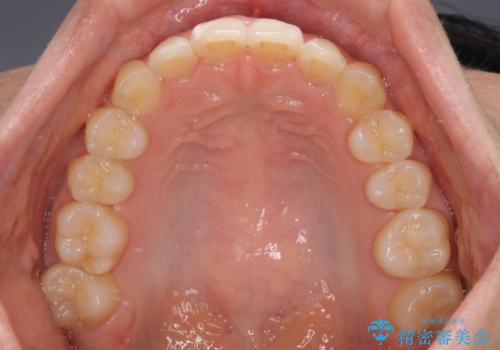

- 上下のクロスバイトと前歯のデコボコを気にして来院された患者様です。

インビザラインを用い、IPR(歯と歯の間を削る)と歯列全体を拡大させることで、歯並びを整えていくこととしました。

下の歯が隠れてしまうほどでしたが、深い咬み合わせも改善され、顎への負担も軽減されました。